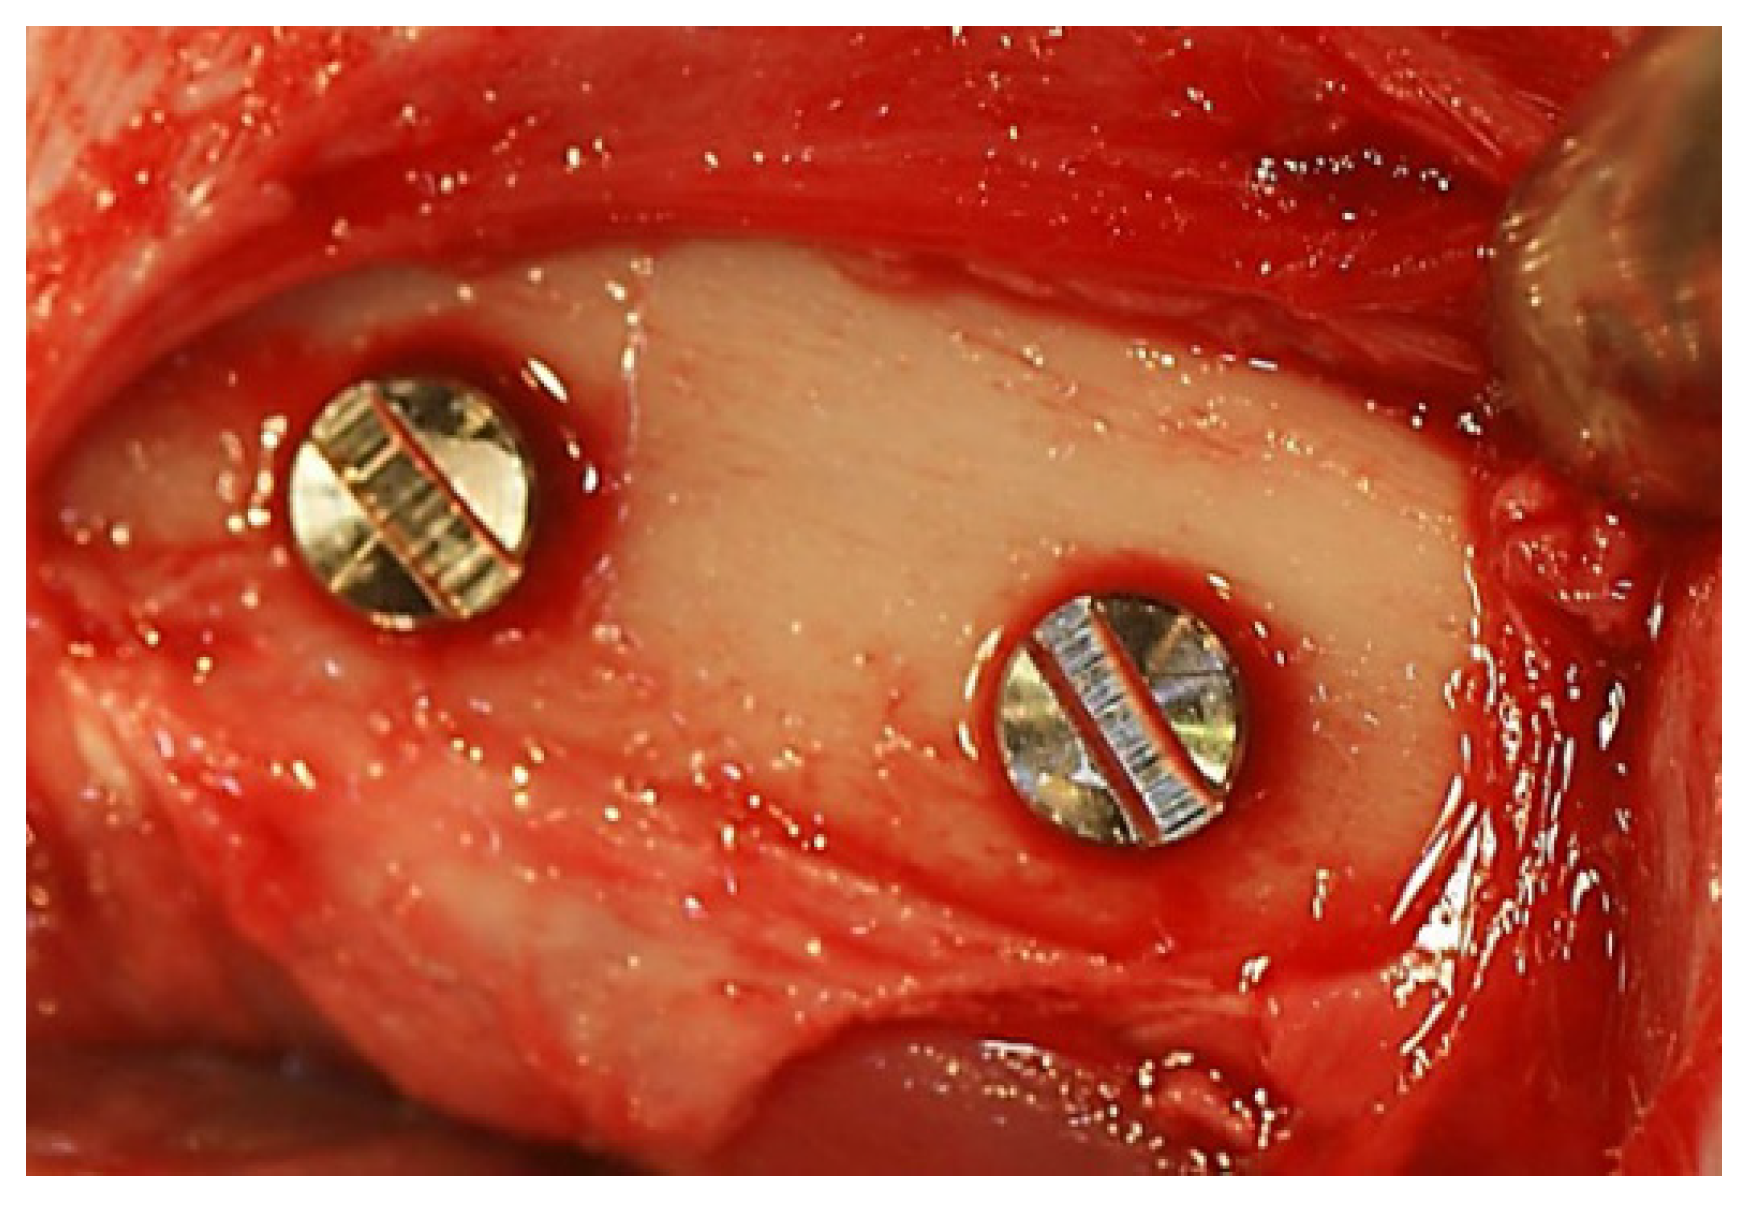

2.1.3. Measurement of Removal Torque and Bone-Implant Contact

3.4. In Vivo Assessment of Osseointegration